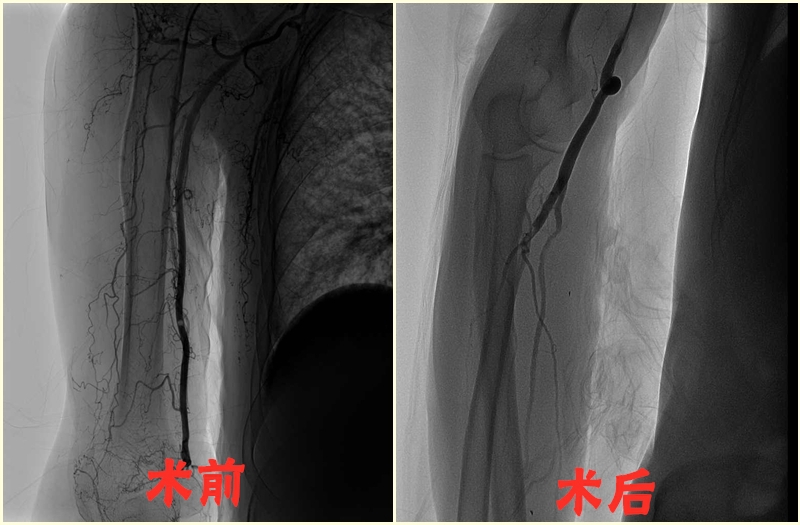

6.上肢动脉闭塞置管溶栓术